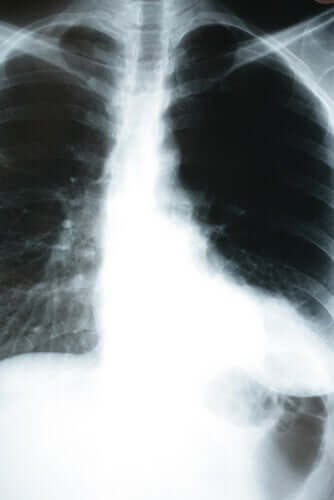

Con la polmonite silenziosa, invece, questo non si verifica. A Codogno, ma anche a New York e in Brasile si è registrato un alto numero di pazienti con polmonite silenziosa che apparentemente stavano bene. La polmonite si è scoperta in modo casuale, attraverso una radiografia del torace o la misurazione dell’ossigeno. Questo tipo di ipossia da Coronavirus, che progredisce inosservata, sta causando molti decessi improvvisi.

In caso di sospetto contagio, si consiglia di misurare la saturazione dell’ossigeno e di eseguire una radiografia toracica. Questo soprattutto se la persona è entrata in contatto con un malato Covid-19 o rientra nelle categorie a rischio.